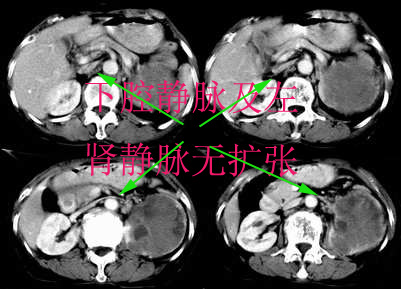

左侧肾癌并肾静脉癌栓.腹膜后淋巴结肿大转移.

顺便说几句。肾癌的转移,肾静脉的转移尤为常见,他可以顺沿静脉直至下腔静脉,这种转移,临床中也不少见,笔者遇到过数例。这种转移对于临床来说有较大意义,直接影响手术的成功、手术的方式等,临床有不少肾癌切除术后,静脉残端复发病例。不知楼主有意还是无意,没有给静脉期,或者左肾静脉充盈的图象。

左肾癌累及左输尿管,左肾静脉无受累征象。